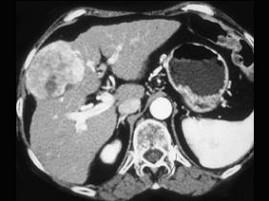

女,55岁,右上腹痛,消瘦乏力3个月,请结合图像诊断为 ( )A、肝脓肿B、肝转移癌C、肝腺瘤D、肝癌E、肝血管瘤

问题 女,55岁,右上腹痛,消瘦乏力3个月,请结合图像诊断为 ( )

选项 A、肝脓肿 B、肝转移癌 C、肝腺瘤 D、肝癌 E、肝血管瘤

答案 D